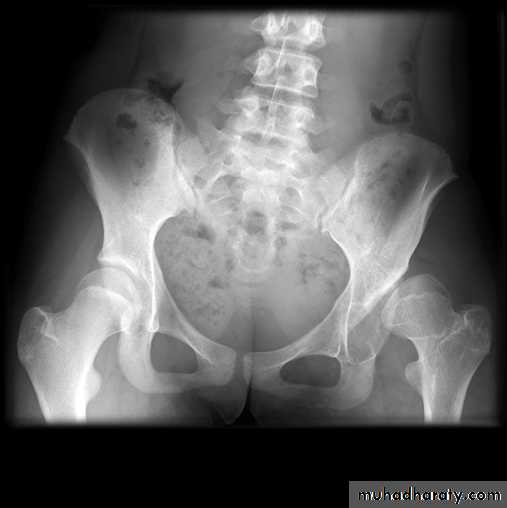

DEVELOPMENTAL DYSFLASIA OF HIP (CONGENITAL DISLOCATION OF THE HIP)

An abnormally lax joint capsule allows the femoral head to fall out of the acetabulum, leading to deformation.

CDH occurs most commonly (70%) in the left hip. Bilateral involvement is seen in 5%.

Radiographic features:

6 months and later

* AP veiw ( femural epiphysis are visualized ):* Superolateral displacement of proximal femur (disturbed shenton’s line )

* Increase in acetabular angle

* Small capital femoral epiphysis

Femoral head is located lateral to Perkin's line

* Other features that are sometimes present

Abnormal sclerosis of the acetabulum

Shallow acetabulum